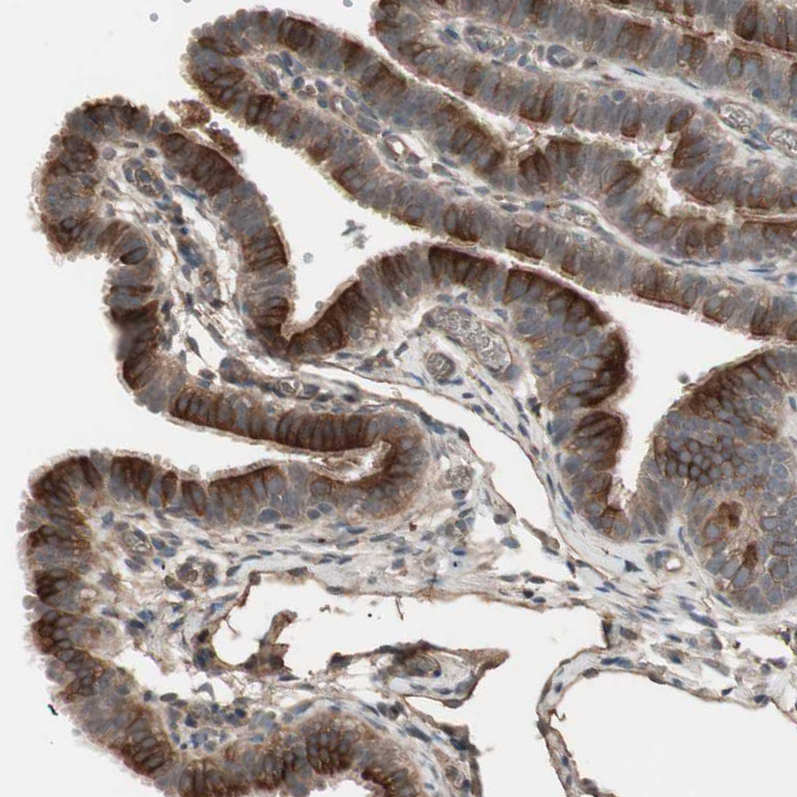

Immunohistochemical staining of human placenta shows strong cytoplasmic positivity in trophoblastic cells.